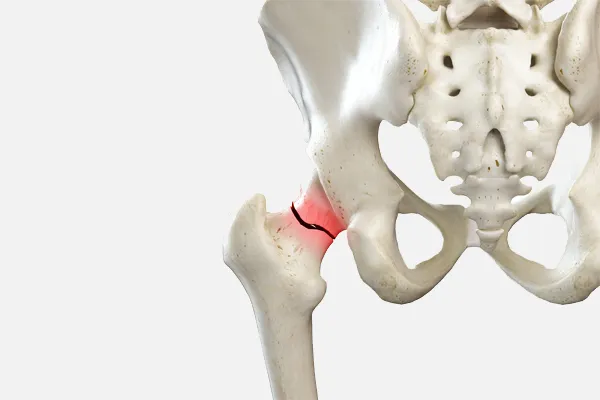

고관절은 특히 뼈 조직이 약해지는 60세 이후에 침대에서 미끄러지거나 넘어지는 등 사소한 충격에도 쉽게 손상되기 쉽습니다. 평균 수명이 증가함에 따라 고관절 골절의 빈도도 늘고 있습니다. 고관절 골절은 대퇴골의 목 부위가 골절되는 대퇴 경부 골절과 목 아래 부위가 골절되는 대퇴골간 골절로 나눌 수 있습니다. 노인에게는 잦은 낙상으로 인해 대퇴골간 골절이 더 흔하게 발생합니다.

대퇴골이 골절되면 심한 통증으로 인해 제대로 걷거나 앉을 수 없지만, 골절 정도에 따라 가벼운 통증만 느끼는 경우도 있습니다. 따라서 넘어진 후 고관절 부위가 붓거나 멍이 든다면 골절을 의심하고 바로 병원을 찾아 치료받는 것이 중요합니다.

고관절 골절 후 합병증으로 인해 폐렴, 혈전색전증, 뇌졸중, 욕창, 요로 감염, 영양실조 등의 위험이 높아질 수 있습니다. 폐렴이 진행되면 심장과 폐 기능이 크게 저하되며, 국민건강보험공단과 대한골대사학회 공동 연구에 따르면 고관절 골절 후 1년 내 사망률은 남성 21.5%, 여성 15.5%로 평균 17%에 달하는 것으로 밝혀졌습니다.